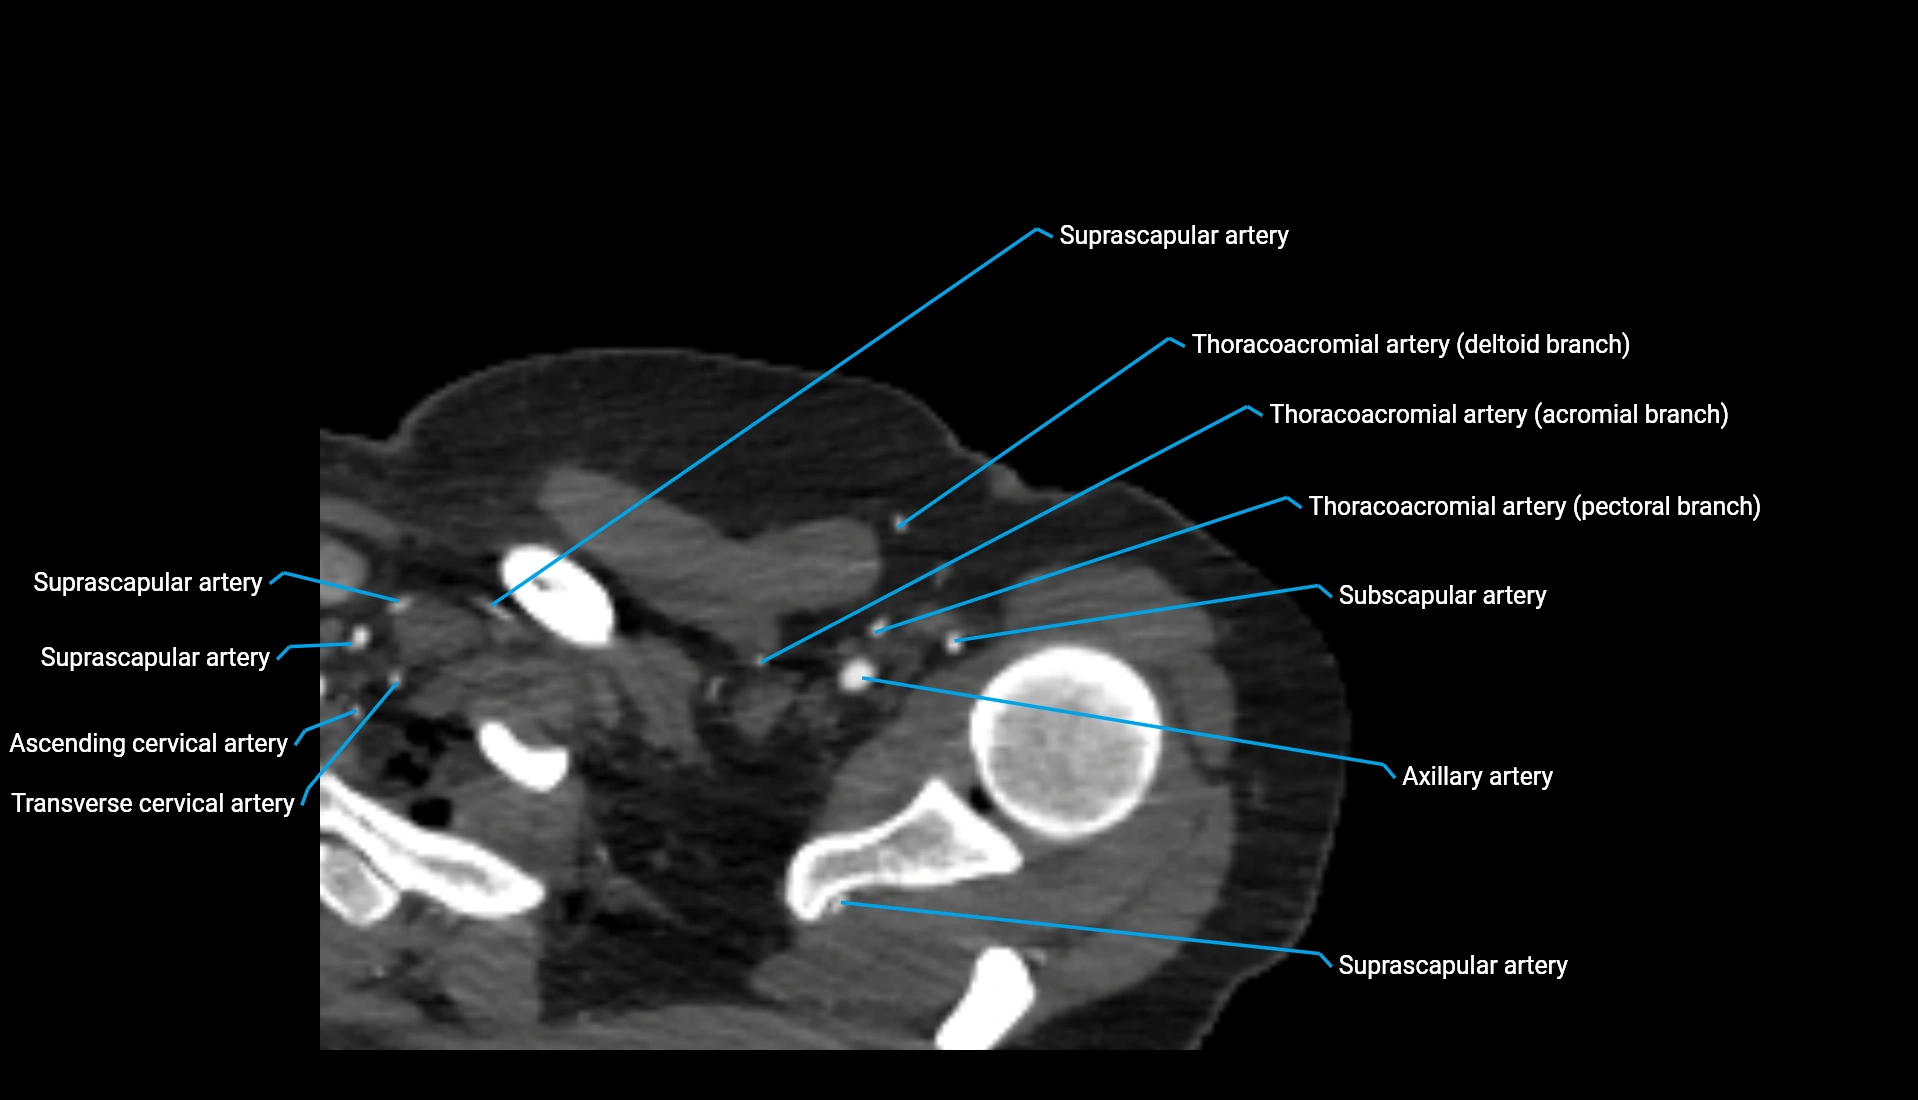

CT Appearance

Non-Contrast CT:

• Cortex: High-density, sharply defined

• Subchondral bone: Dense cancellous matrix

• Articular surface: Smooth concave contour articulating with the capitellum

• Excellent for evaluating bone integrity, alignment, and subtle fractures

Post-Contrast CT:

• Bone: No enhancement

• Joint capsule and synovium: Mild enhancement outlining the joint

• Improves contrast between soft tissues and bony margins

• Useful in detecting subtle joint abnormalities or postoperative changes